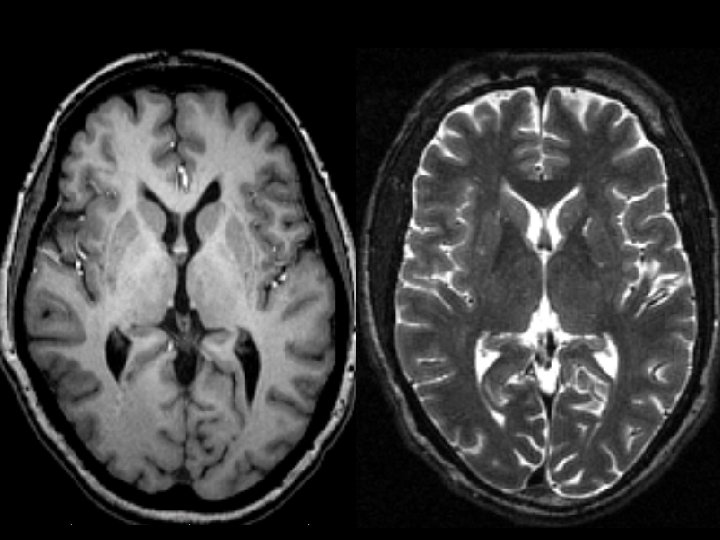

Normal MRI T 1 Weighted

Normal MRI T 2 Weighted